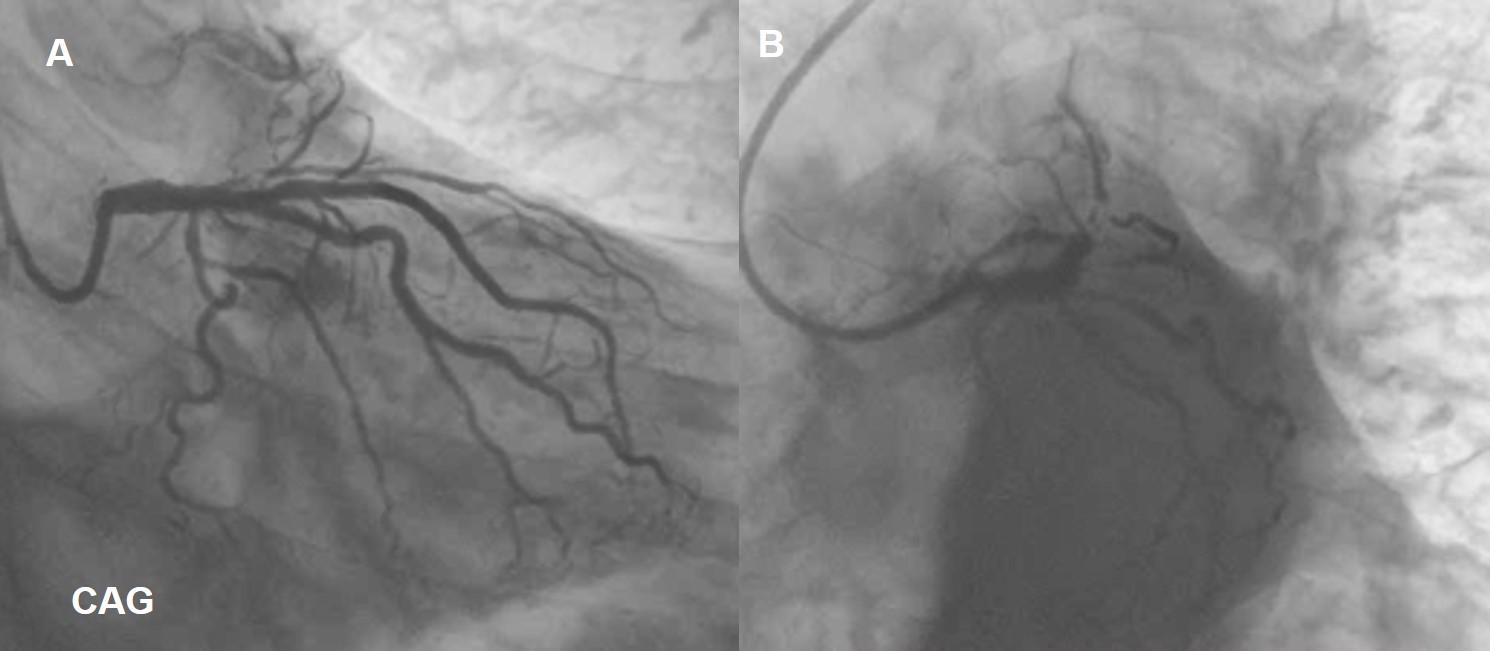

Coronary angiogramrevealed double vessel disease with D1 Osteal 90% Stenosis, Ramus-osteoproximal 90% Stenosis.